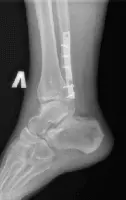

Стандартний рентгенографічний аналіз області гомілковостопного суглоба включає візуалізацію 2 видів: прямого заднього та бокового. У деяких випадках роблять знімок у косій проекції.

Прямий задній вигляд дозволяє оцінити стан суглобової щілини, яка має ширину 3-4 мм. Також на знімку можна розглянути кісточку, таранну та гомілкові кістки. Щоб досліджувати їх детальніше, використовується коса проекція.

Бічний вигляд дозволяє виявити переломи, вивихи та суглобові випоти навколо гомілкостопа. Крім того, проекція допомагає в оцінці тяжкості травм кістки п’яти шляхом вимірювання кутів Беллера і Гиссана, які в нормі рівні 20-40° і 94-136° відповідно.

При розгляді рентгенограм вивчаються м’які тканини на наявність набряку. Скупчення рідини в області зчленування латеральної та медіальної кісточок є ознакою переломів та травм зв’язок. Випіт може бути ідентифікований за наявності ущільнень тканин спереду та ззаду суглоба.

На знімках погано видно зв’язки та сухожилля, проте добре проглядається ахілове сухожилля. Його нормальний діаметр у середньому становить 6 мм. Значення параметра понад 8 мм вказує на патологію сухожиль, причиною може бути дистрофічне ураження найближчих м’язів, розрив, запальні артропатії, післяопераційні зміни.